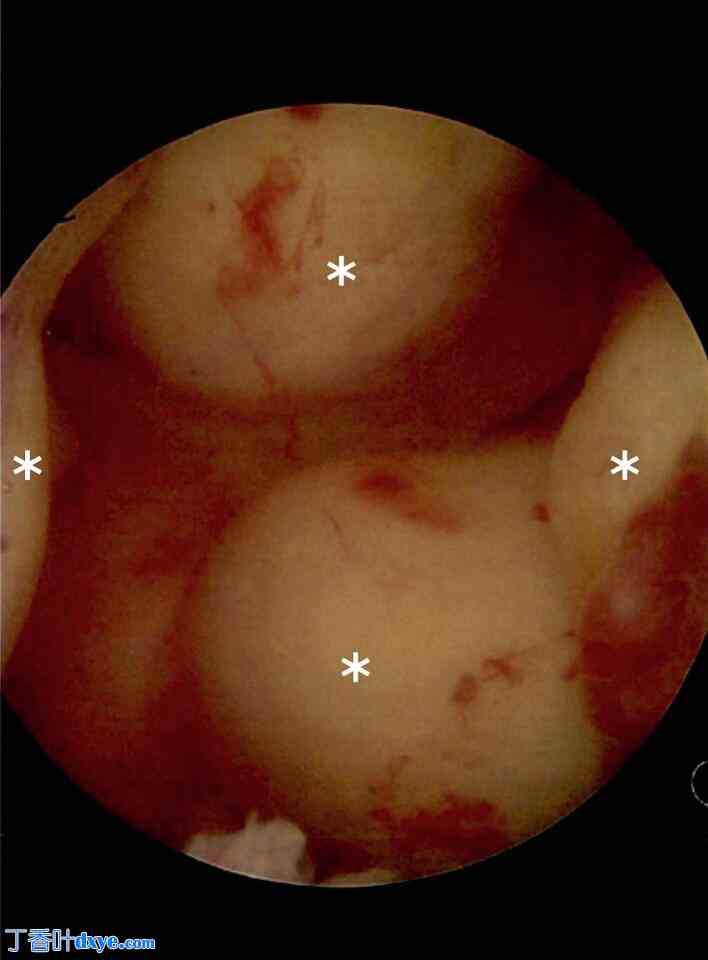

一位35岁的东南亚女性,因严重月经过多经医生转诊至本院,诊断为多发性黏膜下和肌壁间子宫肌瘤,并导致慢性贫血。来院前,患者曾接受激素避孕药等保守治疗,但症状未得到缓解。患者无家族史,不吸烟、不饮酒,且既往未接受过手术。体格检查显示子宫增大。在接受促性腺激素释放激素激动剂戈塞林(Goserilin)3个月的药物治疗后,患者选择接受宫腔镜子宫肌瘤切除术。术前磁共振成像 (MRI) 显示患者有多发性黏膜下子宫肌瘤(图1)。

图 1.

轴向盆腔 MRI 扫描显示两个黏膜下肌瘤(标有星号),导致子宫内膜变形(箭头所示)。